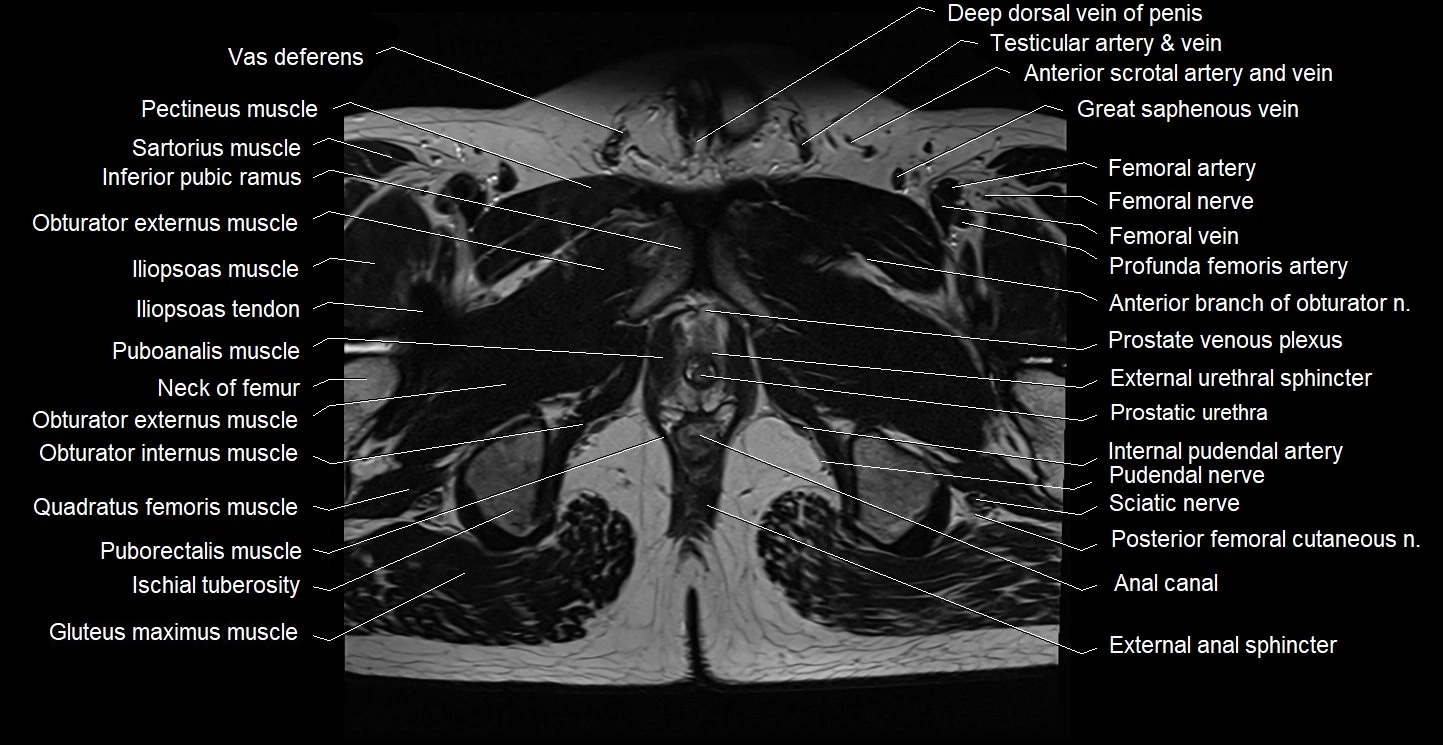

- Anal canal

- External anal sphincter

- External urethral sphincter (male)

- Femoral nerve

- Femoral vein

- Gracilis muscle

- Pectineus muscle

- Posterior femoral cutaneous nerve

- Prostatic urethra

- Puboanalis muscle

- Puborectalis muscle

- Pudendal nerve

- Quadratus femoris muscle

- Sciatic nerve